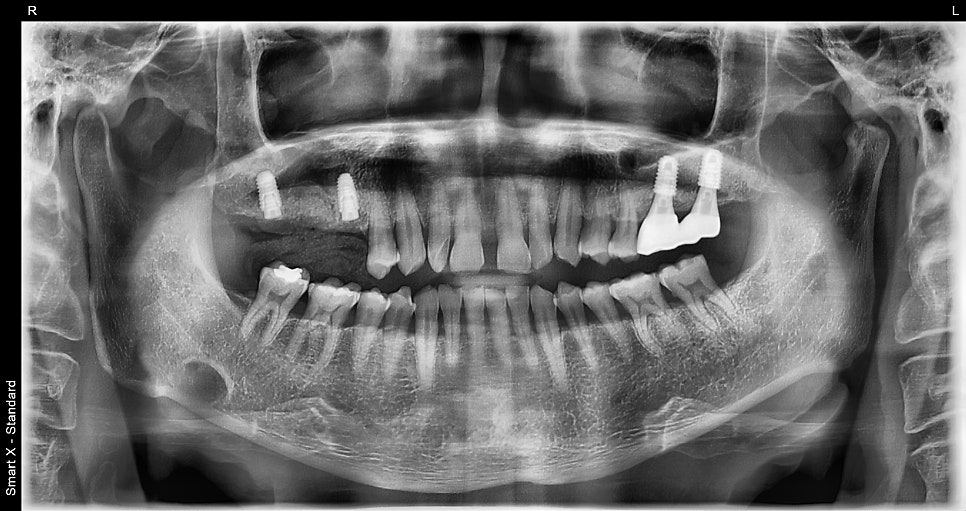

- Early January: Immediate implant placement after extracting the tooth with severe inflammation on the right (#17 and #15, two implants placed / allograft bone graft) + overall gum treatment performed at the same time (for the prevention of gum inflammation and bone loss)

This panoramic X-ray shows the immediate implant placement after extraction of #16 (the first upper right molar) and #15 (the second upper right premolar).

Considering the patient’s smoking status, osseointegration may have progressed quickly, but taking into account gum condition and systemic diseases such as hypertension and diabetes, the surgery was safely divided into first and second stages.

※ If needed, a healing abutment can also be connected on the day of extraction to complete the crown faster.